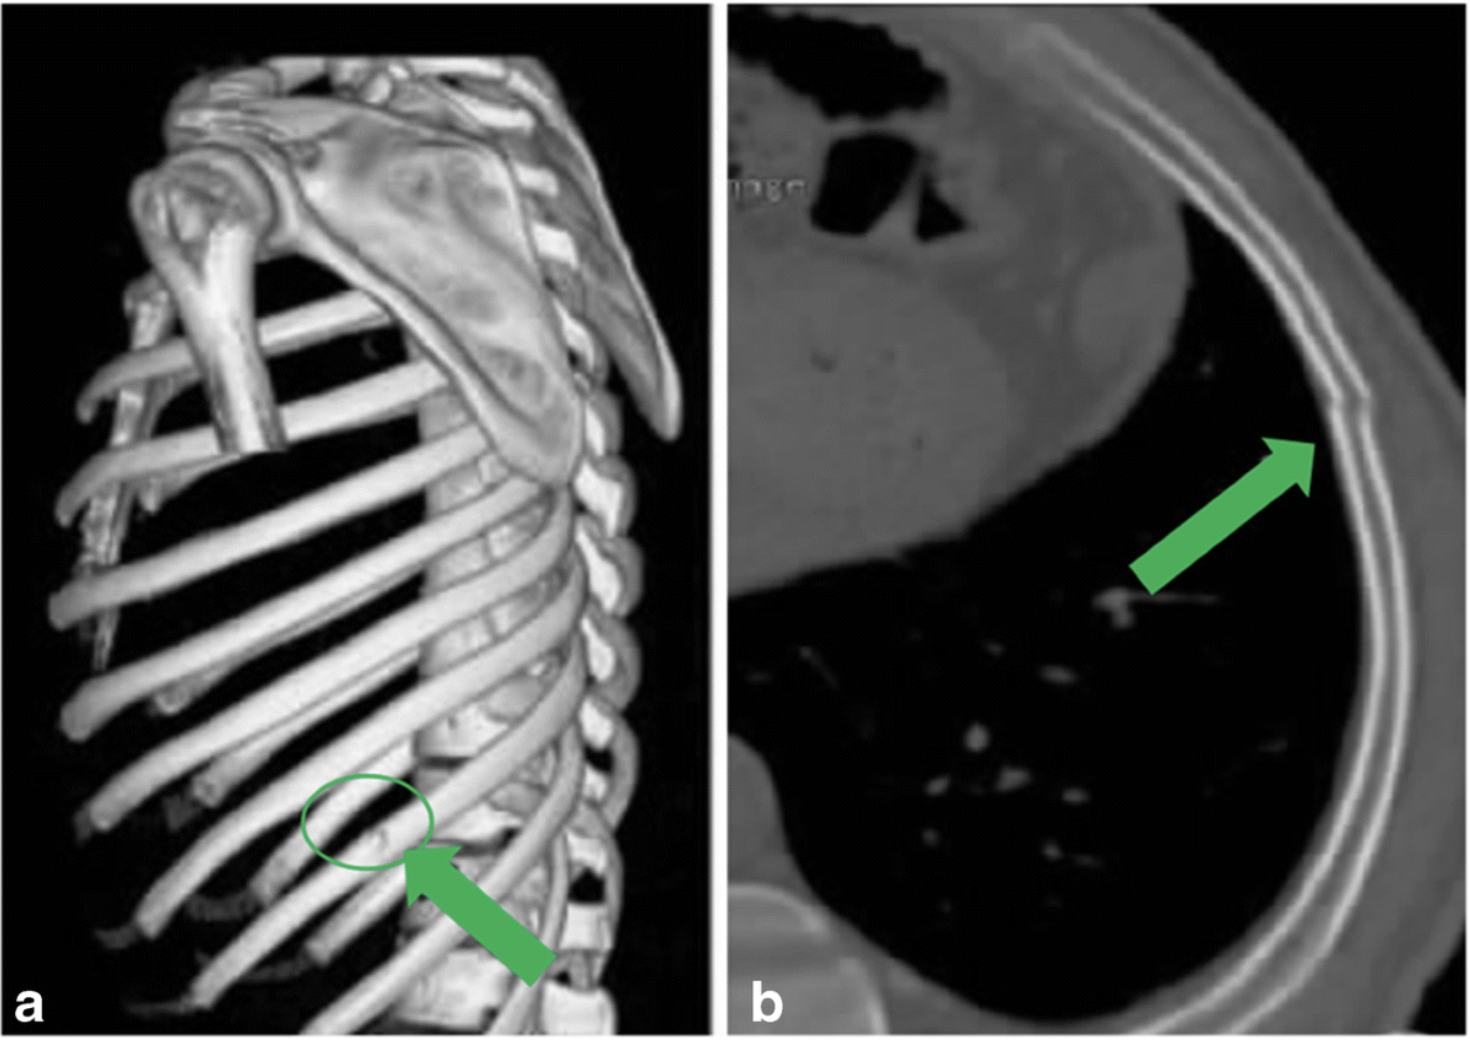

第10肋骨骨折のCT 3-D再構築画像(a)と水平断(b).

X線写真では写りにくい, ヒビが入ったような骨折(亀裂骨折)でも, CTでは見つけることができます.

引用元:Hu J. Missed rib fractures on initial chest CT in trauma patients: time patterns, clinical and forensic significance. Eur Radiol. 2021. 31.

胸部CTの結果, 肋骨が3本骨折していました. 通常のX線写真では写らないようなヒビ(亀裂骨折)でした. このような骨折を見逃さないようにするためには, CTで撮像した画像を立体的に再構築して見る必要があります(上図a).